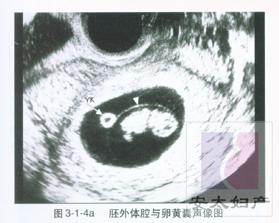

怀孕两个月指妊娠的5~8周。 在此时期,胎儿的成长满7周时,胚胎身长约2.5厘米,体重约4克。心、胃、肠、肝等内脏及脑部开始分化,手、足、眼、口、耳等器官已形成,已越来越接近人的形体。绒毛膜更发达,胎盘形成、脐带出现,母体与胎儿的联系非常密切。

怀孕2个月胎儿b超图1

怀孕2个月胎儿b超图2